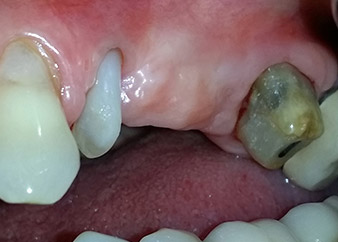

Fig. 1: En una paciente de 58 años, la radiografía previa a la intervención mostraba una lesión periodontal apical en la pieza dental 24, así como una pérdida horizontal de hueso alveolar en el segundo cuadrante.

Mujer de 58 años de edad, que además es una apreciada colega y amiga, y se quejaba de dolor y de un aumento en la movilidad del pilar del puente de la pieza dental 24. También había inflamación periodontal, con bolsas de una profundidad de 7 mm en sentido mesiobucal y más de 12 mm en sentido distal, así como furcación de tercer grado. Asimismo, la radiografía reveló una lesión periodontal extensa alrededor de la región apical de la pieza dental 24 (figura 1) tratada previamente con endodoncia (alio loco).

Un año antes, las piezas dentales 25 y 26 se habían extraído por razones traumáticas y endo-periodontales antes de la colocación del puente. Se diagnosticó una lesión endo-periodontal combinada en la pieza dental 24, pero su componente etiológico principal no estaba claro. La paciente declaró su voluntad de mantener el pilar del puente de las piezas 24 y 27 y afirmó que no aceptaría una prótesis extraíble final, ni siquiera provisional. Por lo tanto, se acordó intentar por todos los medios conservar ambos dientes, a pesar del mal pronóstico que mostraban las pruebas radiológicas y clínicas.